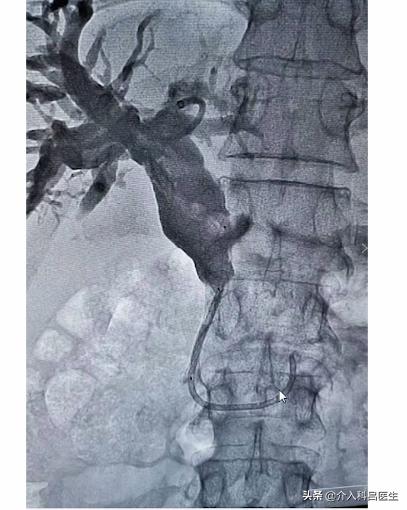

我们经皮肝穿,在腰旁扎个针,直接就扎到肝脏里面,直接就能进到胆管里面。这是我们的造影,可以看到胆管都是扩张的,胆总管也是明显扩张的。

肿瘤侵犯的地方,把胆管给侵犯压迫了,胆汁都淤积在里面,人就成“小黄人”了。于是我们在肿瘤地方放了支架,考虑病人的情况,我们放置的国产支架,非常便宜。支架张开,胆汁就可以顺着支架进入了小肠里面,胆汁还能够参与消化。